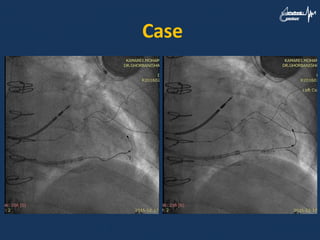

Case • A 73yr man was a case of ischemic cardiomyopathy with VT and LBBB • CRT-D was done successfully and there was improvement his heart failure • There was LV lead dislocation after two yeras

• 62.

• 63.

• 64.

• 65.